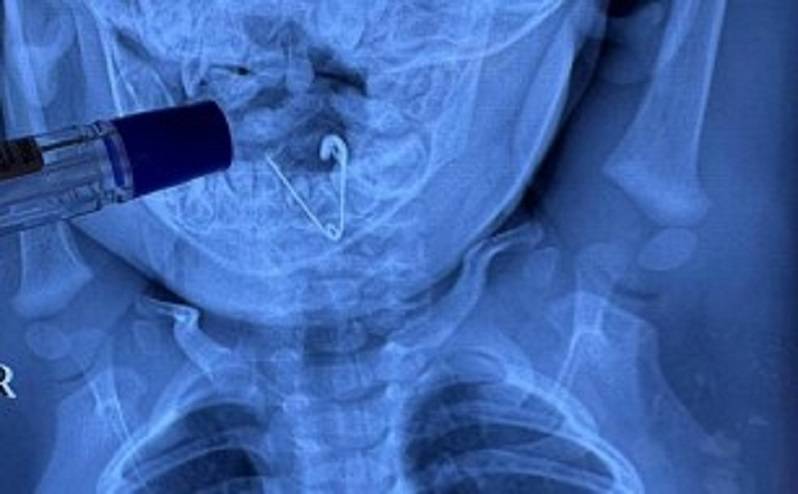

Бригада медиков госпитализировала маленького пациента в приемное отделение Центральной районной больницы Черниговки. Здесь ему сделали обзорную рентгенографию органов грудной клетки. В пищеводе была обнаружена тень инородного тела.

Оперативно ребенка доставили в Краевую детскую клиническую больницу №1 Владивостока, где у врачей огромный опыт по извлечению самых сложных инородных предметов. Здесь малышу провели повторное рентгеновское исследование, подтвердившее диагноз. На снимке была четко видна открытая булавка. Врачи удалили ее при помощи щипцов под контролем эндоскопической техники. Ребенок перенес операцию хорошо и вскоре будет выписан домой.